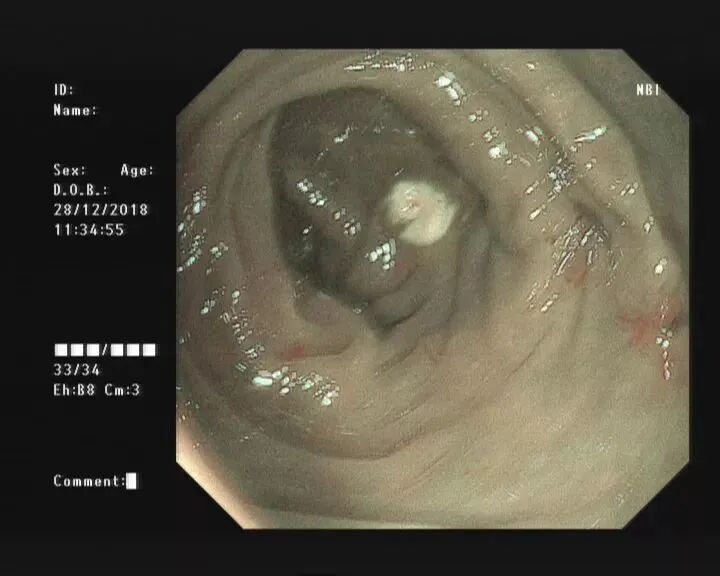

当黄斑马导丝及导管置入阑尾腔时,可见脓性分泌物涌出。随之进行阑尾腔冲洗;

X线下,阑尾腔内注入造影剂显示阑尾腔的形态(椭圆形线圈),如有粪石(黑箭头),则行球囊取石术。并确认有无阑尾穿孔。

通过内镜下置入球囊导管或取石网篮,将粪石取出,原理如ERCP取石术。(黑箭头示取出的粪石)。